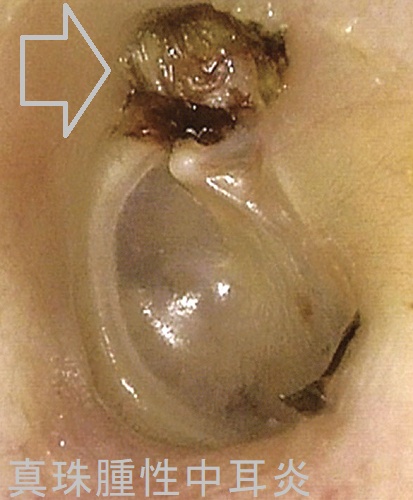

真珠腫性中耳炎(cholesteatomatous otitis media)は慢性中耳炎の重症型です。真珠腫とは、中耳側に凹んだ鼓膜の一部へ上皮細胞が侵入・増殖したもので、骨を溶かして進行します。

真珠腫の進行によって

- 伝導性難聴;耳小骨の破壊

- 感音性難聴・めまい;内耳の破壊

- 顔面神経麻痺

- 髄膜炎・脳膿瘍;頭蓋内へ浸潤

化膿性中耳炎と真珠腫性中耳炎に対する根治的治療は、真珠腫の摘出と鼓室形成術。